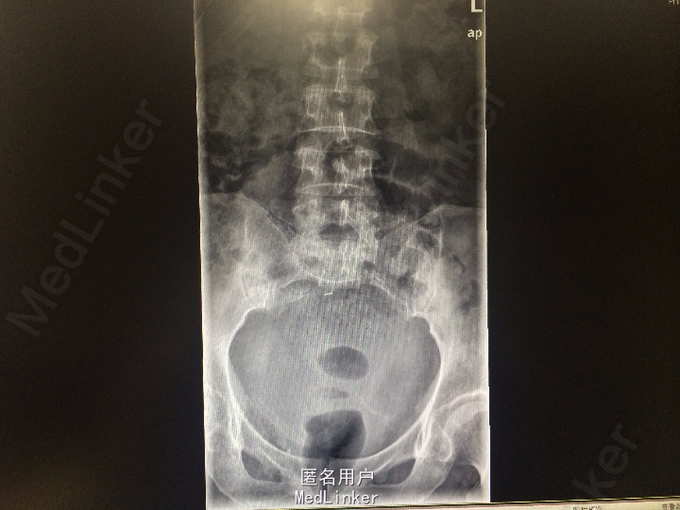

老年女性 主诉:腰背痛半年余,大小便失禁1周。 病史:患者于半年前腰部扭伤后,出现腰痛、腰部无力,需借助外力站立和行走。自诉四肢肌肉力量间断出现减弱,容易出现肌肉僵直,并有肌肉颤动感。半年来,患者多卧床休息,未接受正规治疗。10余天前,出现胸部疼痛,并向背部放射,病人烦躁、易怒,难以入睡、胃纳差、大便次数少。1周前出现大小便失禁,体重近1月下降10余斤。

查体:脊柱生理弯曲存折,腰椎棘突间触痛(-),双侧腰椎旁叩痛(-),活动自如,关节无红肿,双侧下肢肌群肌力正常,双侧下肢外侧皮肤痛、温觉正常,未引出病理性反射,尾骨未触及。 辅查:外院X线:腰骶角增大,提示腰椎失稳可能;腰椎轻度退行变;S3以下骨质结构缺如。

诊断:骶尾部肿物:脊索瘤? 处理:完善各项检查后,为明确具体病理类型行骶尾部肿瘤穿刺活检术,病理明确后行腹腔镜辅助下骶尾部肿瘤切除术。